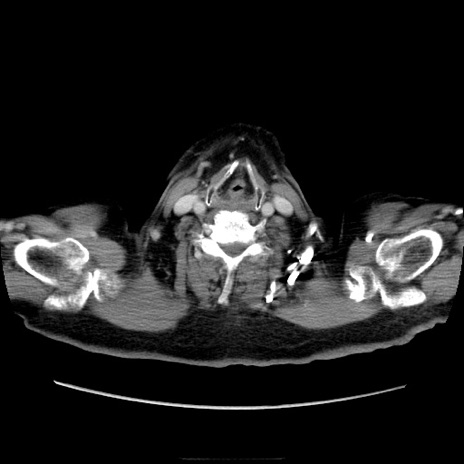

症例21(横断像)

【症例】70歳代男性

【主訴】腹痛

【現病歴】肝硬変・肝細胞癌にてかかりつけの方。約9時間前に食後より腹痛出現。症状が徐々に増悪し、嘔吐出現したため来院。

【既往歴】肝硬変、肝細胞癌(RFA、TACE後)

【身体所見】意識清明、表情苦悶様、BT 36℃、BP 129/78mmHg、P 88bpm、SpO2 97%(RA)、右上腹部から心窩部にかけて圧痛あり、反跳痛なし、筋性防御あり。

【データ】WBC 5800、CRP 0.16